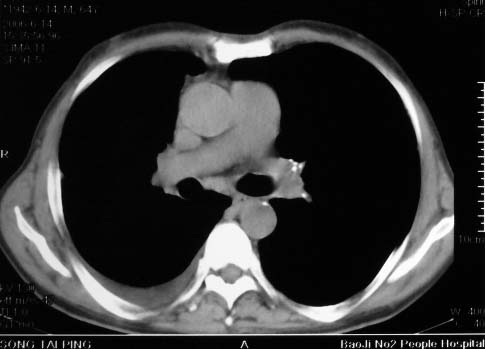

病史:男,64岁,咳血,咳痰,发热3天,wbc---1.2万

影象表现:右肺上叶大片状、网格状及索条致密影,蜂窝影,其内参杂斑点状小结节,密度不均匀,内见含气支气管像,纵隔内见肿大淋巴结.

抗炎10天后无好转出现胸水,考虑:肺结核合并间质纤维化

抗感染病变无明显改善,右上叶大片状增弥不均匀病灶,夹杂网状及支气管充气像,肺门纵隔淋巴结肿大,右侧胸腔积液。考虑1混合感染伴肺间质改变[警惕特殊感染,如真菌]。2细支气管肺泡癌。建议结合临床及进一步检查[如痰,胸水脱落细胞检查及支气管镜检灌洗或穿刺活检

右肺上叶见大片状及索条致密影,密度不均,内见含气支气管症,纵隔内见肿大淋巴结.

影象表现:右肺上叶大片状、网格状及索条致密影,蜂窝影,其内参杂斑点状小结节,密度不均匀,内见枯枝样含气支气管像,纵隔内见肿大淋巴结.胸膜广泛增厚,前胸壁似受累.少量胸腔积液.纵隔内淋巴结的直径>1.5cm.右侧胸廓体积缩小.考虑:1 肺结核合并间质纤维化 2 细支气管肺泡癌

右肺上叶大片状、网格状及索条致密影,蜂窝影,其内参杂斑点状小结节,密度不均匀,内见枯枝样含气支气管像,纵隔内见肿大淋巴结.胸膜广泛增厚,前胸壁受累增厚.少量胸腔积液.纵隔内淋巴结的直径>1.5cm.右侧胸廓体积缩小.考虑: 细支气管肺泡癌并肺内癌性淋巴管炎。